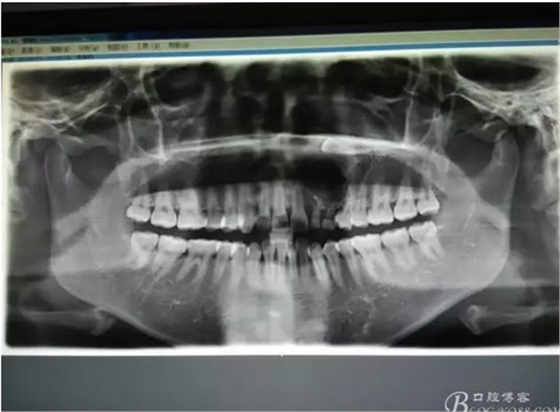

圖1。術(shù)前的CBCT影像檢查:22位于鼻底下方,23位于24、25的根方。左側(cè)乳Ⅱ、Ⅲ根方顯示囊性改變,囊腔內(nèi)大量致密鈣化團(tuán)塊,密度高。

圖21.術(shù)中拍全景片,看是否有牙瘤殘留,發(fā)現(xiàn)左側(cè)乳Ⅱ根尖區(qū)還有少量致密鈣化物,建議拔除左側(cè)乳Ⅱ、,患者要求保留兩個(gè)乳牙。經(jīng)協(xié)商,遺留極少量鈣化物,不影響整體愈合。通過(guò)骨腔探查,發(fā)現(xiàn)左側(cè)乳Ⅱ、Ⅲ根尖區(qū)未破壞,骨壁尚完整。同意遺留部分鈣化物。有點(diǎn)缺憾,為了保留乳牙和患者的美觀及功能。定期觀察遺留部分的發(fā)展變化